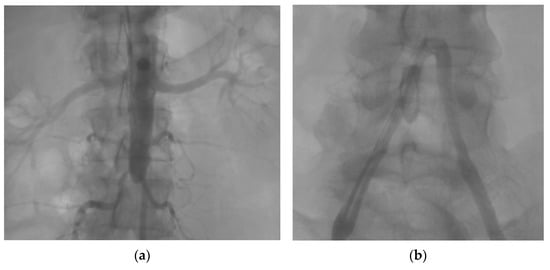

Chronic Complete Distal Aortic Occlusion and Pulmonary Embolism—Atypical Antiphospholipid Syndrome?

Caraiola, S.; Voicu, L.; Cașu, D.; Armășoiu, E.; Cobilinschi, C.O.; Mihai, E.; Ionescu, R.A. Chronic Complete Distal Aortic Occlusion and Pulmonary Embolism—Atypical Antiphospholipid Syndrome? Diagnostics 2023, 13, 1346. https://doi.org/10.3390/diagnostics13071346